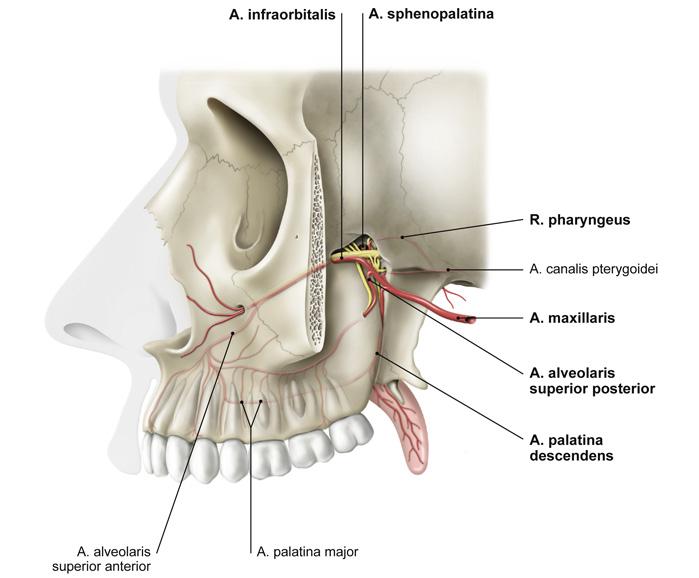

Fig 3.10a: a. maxillaris - sfenomaxillair deel

|

|

Fig 3.10c: a. maxillaris - sfenomaxillair deel - verhemelte

-

a palatina descendens

-

a palatina maior

aa palatinae minores